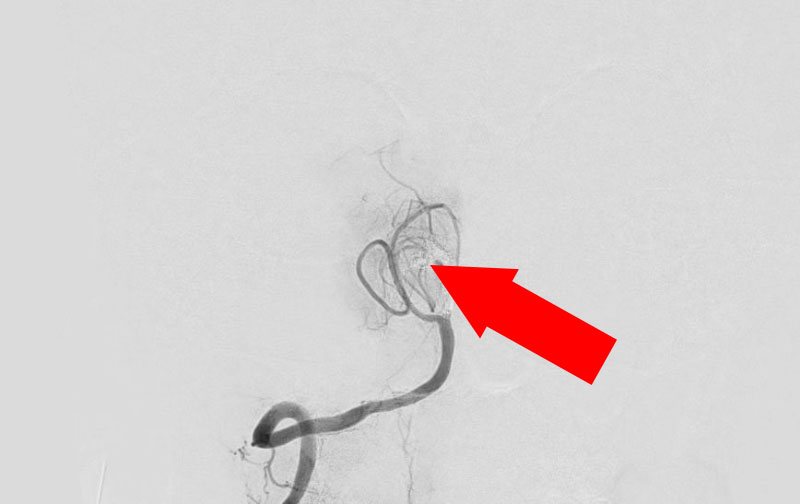

左椎骨動脈後下小脳動脈分岐部動脈瘤

70代

院内外来

No.1628 手術前

No.1628 手術中

No.1628 手術後